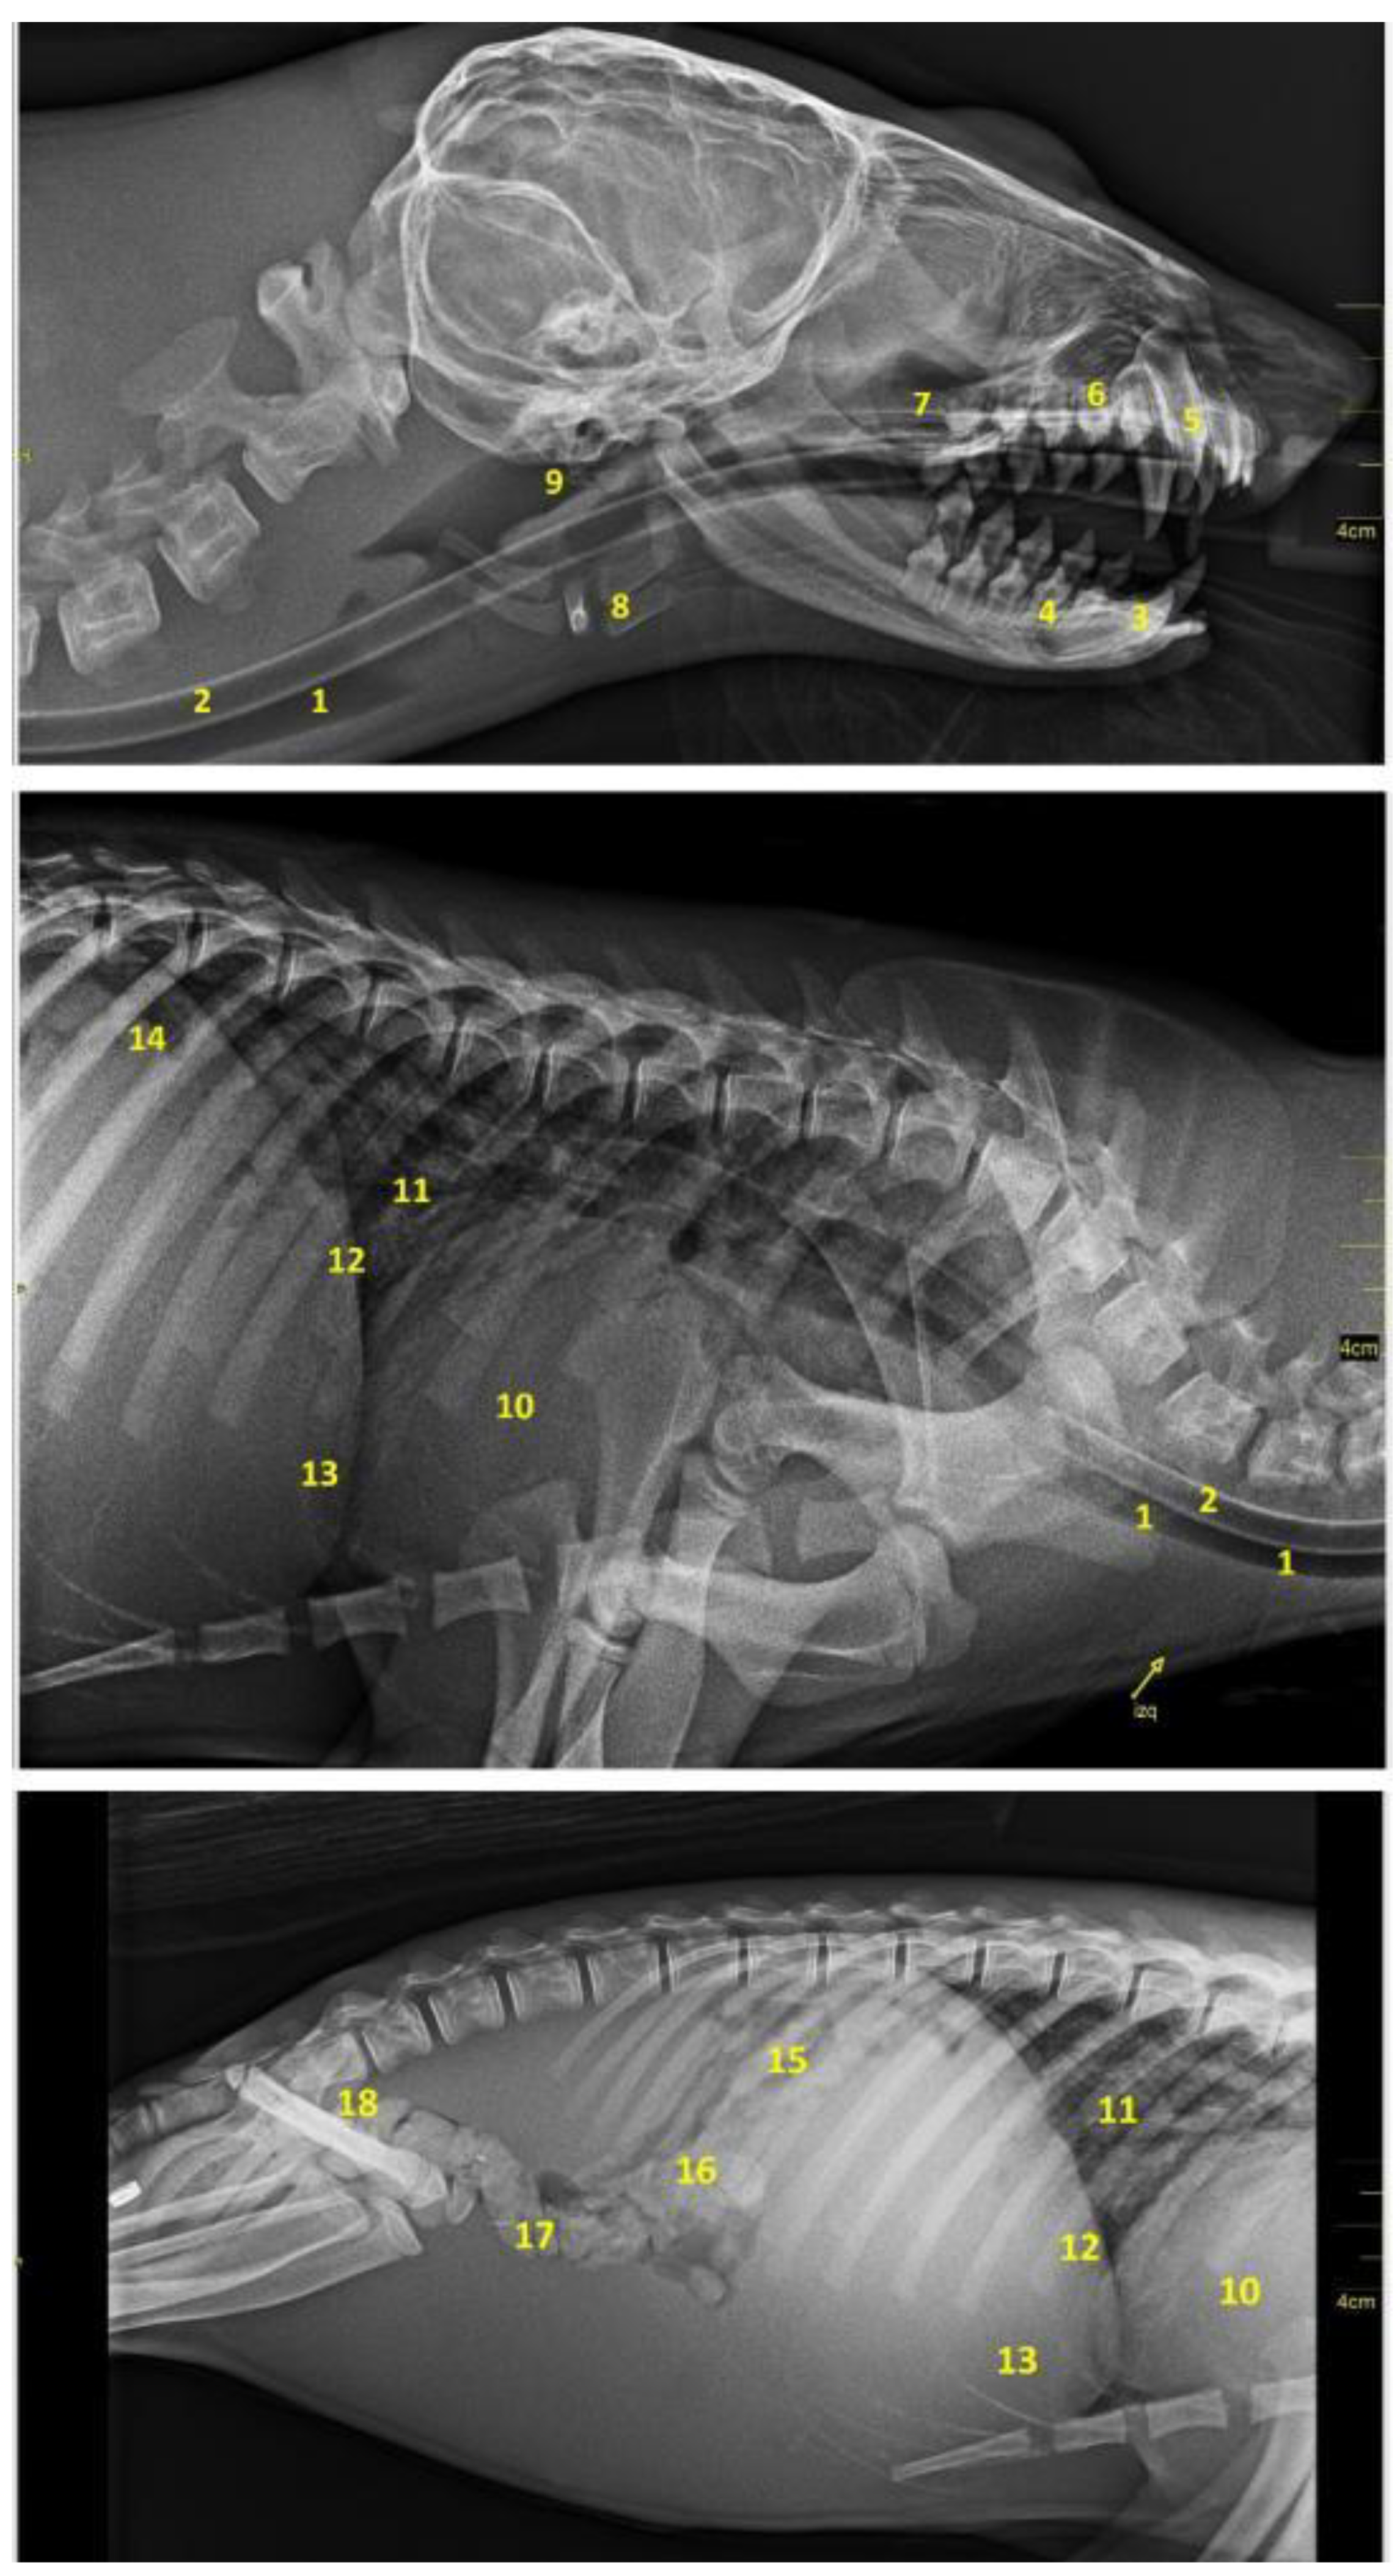

3.8. Radiology

As mentioned, the anatomical description of the digestive system of the Arctocephalus australis was completed with a radiological study. Figure 28 shows the appearance of the main digestive viscera and its topographical relationships.

Figure 28. Radiographic images in laterolateral projection of the head, neck and cavities. (1) Trachea; (2) esophagus; (3) lower right canine; (4) lower right 2nd molar; (5) upper right canine; (6) maxillary right 2nd premolar; (7) maxillary; (8) hyoid; (9) pharynx; (10) cardiac profile; (11) bronchial tree; (12) diaphragmatic border; (13) liver; (14) stomach; (15) jejunal loops; (16) ascending colon; (17) transverse colon; (18) descending colon.